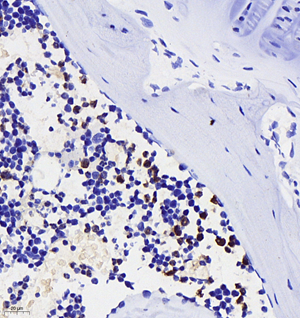

IHC/IF | Human, Mouse, Rat | 1: 200-1: 2000 | bone, liver, liver+LPS |